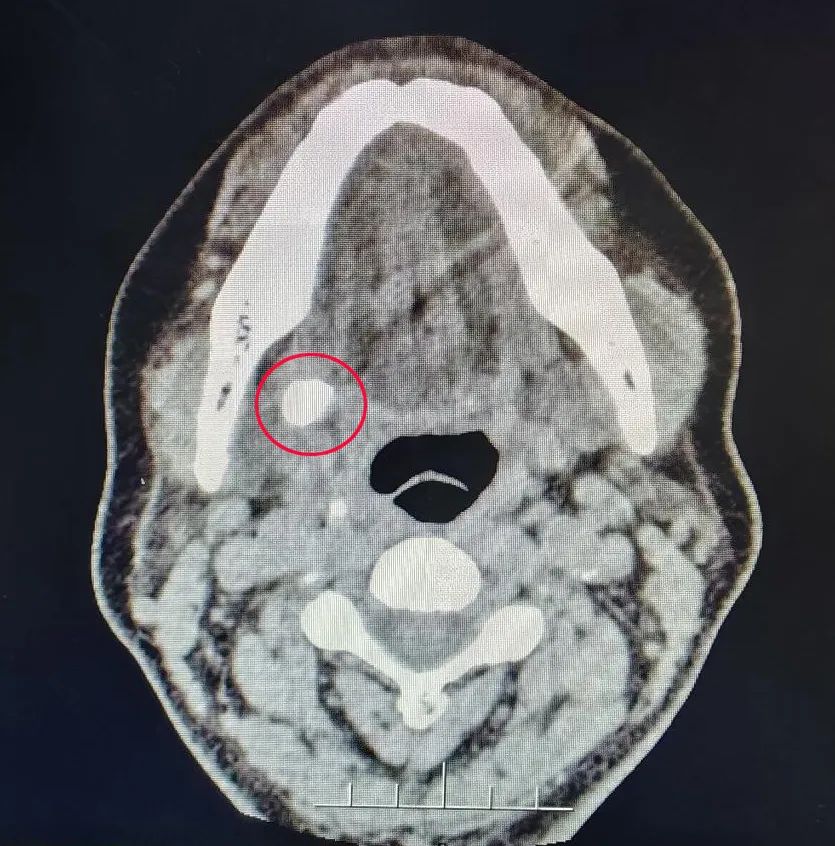

西海岸新区的薛女士近几个月来,每次餐后右侧颌下部位都会肿胀,半小时至一小时后方能缓解。区中心医院口腔科接诊后,初步判断是颌下腺导管结石,由于结石在导管中阻塞了唾液的排出,导致局部肿胀。通过CT检查发现其右侧颌下腺导管内存在高密度结石影像,因此确诊为颌下腺导管结石。

面对薛女士结石体积大、位置特殊的挑战,传统手术不仅会切除颌下腺,还会留下面部疤痕,甚至可能造成面部神经受损,导致面瘫。为避免这些风险,口腔科团队进行充分术前讨论,并与患者沟通,最终决定采用内窥镜技术,从口腔内进行结石取出,实现了微创、低并发症、器官保存的手术目标。

在山东大学齐鲁医院王勇主任医师的技术指导下,区中心医院口腔科李大纲副主任医师、赵鹏主治医师及杨连柱主治医师团队,克服了导管口狭窄、管腔塌陷、口腔内视野有限等手术难点,利用内窥镜精准定位并成功取出两颗结石,展示了国内领先的微创技术水平。